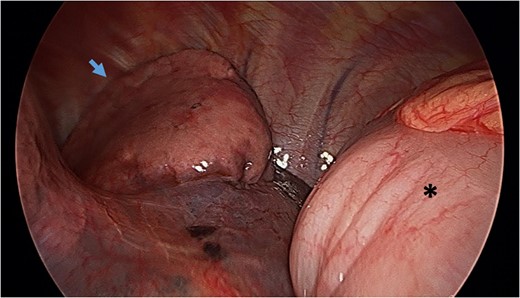

Reduction of transverse colon into abdominal cavity. The spleen is visible adjacent to the transverse colon. Black asterisk (*) indicates a loop of transverse colon. Blue broken arrow indicates the diaphragmatic defect that was extended to successfully reduce the colon.